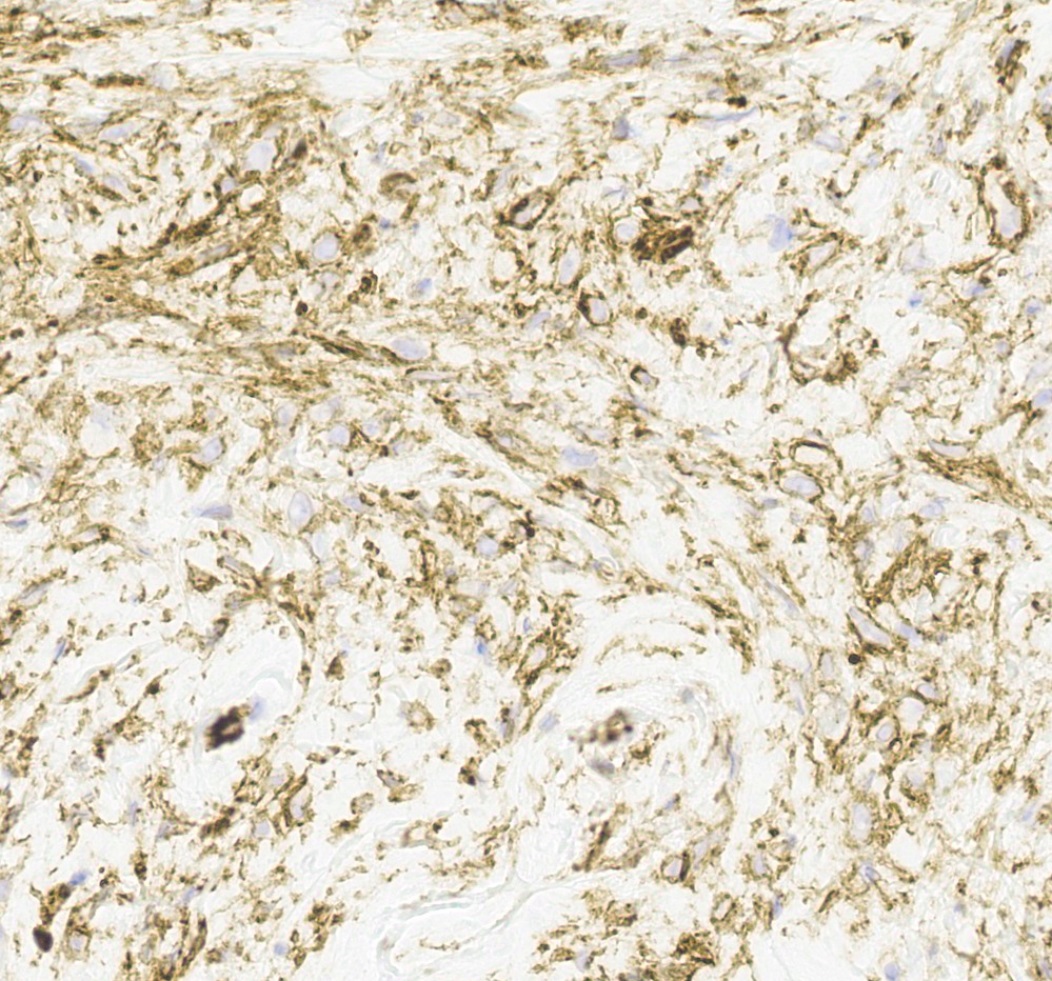

Microscopic (histologic) images

Positive stains

- Desmin (91%), vimentin, ER, PR, AR, BCL2, CD10, CD99 (Histopathology 2000;36:515, Virchows Arch 2007;450:727)

- CD34 (89%) diffuse and strong characteristic but may uncommonly show absent / focal expression (Am J Surg Pathol 2016;40:361, Breast J 2018;24:55)

- H-caldesmon if smooth muscle differentiation / leiomyomatous variant (Hum Pathol 2016;58:54, Histopathology 2003;42:233)